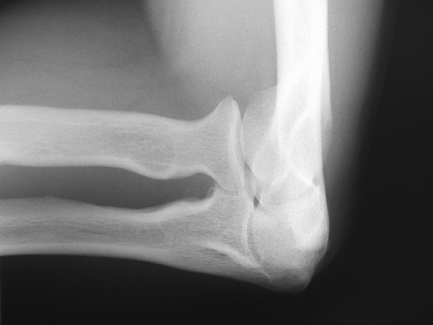

The lateral radiograph (Fig. 48-1B) clearly

shows the coronoid and olecranon processes, as well as the associated

fossa. The radial head overlies the coronoid, but should still allow

adequate visualization of both structures. Adequacy of the lateral view

can be determined by the target sign of three concentrically larger

circles seen in the distal end of the humerus. These rings represent,

from inside out, the minimum dimension of the trochlea, the capitellum,

and the medial rim of the trochlea. Malrotation by as little as 5

degrees will disrupt this appearance. Anterior and posterior fat pads

can be seen in situations of intra-articular distension (Fig. 48-2). The supinator fat stripe can be displaced by swelling associated with radial head fractures.

Figure 48-1 A: Anterior-posterior (AP) view of the elbow in full extension. B: Lateral view of the elbow. Note concentric circles representing, from the center out, (A) trochlear sulcus, (B) capitellum, and (C) medial wall of the trochlea.